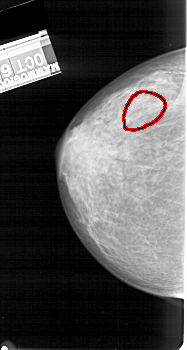

A_1393_1.LEFT_MLO

LEFT_MLO LINES 5491 PIXELS_PER_LINE 2836 BITS_PER_PIXEL 12 RESOLUTION 43.5 OVERLAY

FILE: A_1393_1.LEFT_MLO.OVERLAY

TOTAL_ABNORMALITIES 1

ABNORMALITY 1

LESION_TYPE CALCIFICATION TYPE AMORPHOUS DISTRIBUTION SEGMENTAL

ASSESSMENT 4

SUBTLETY 2

PATHOLOGY BENIGN

TOTAL_OUTLINES 1

BOUNDARY